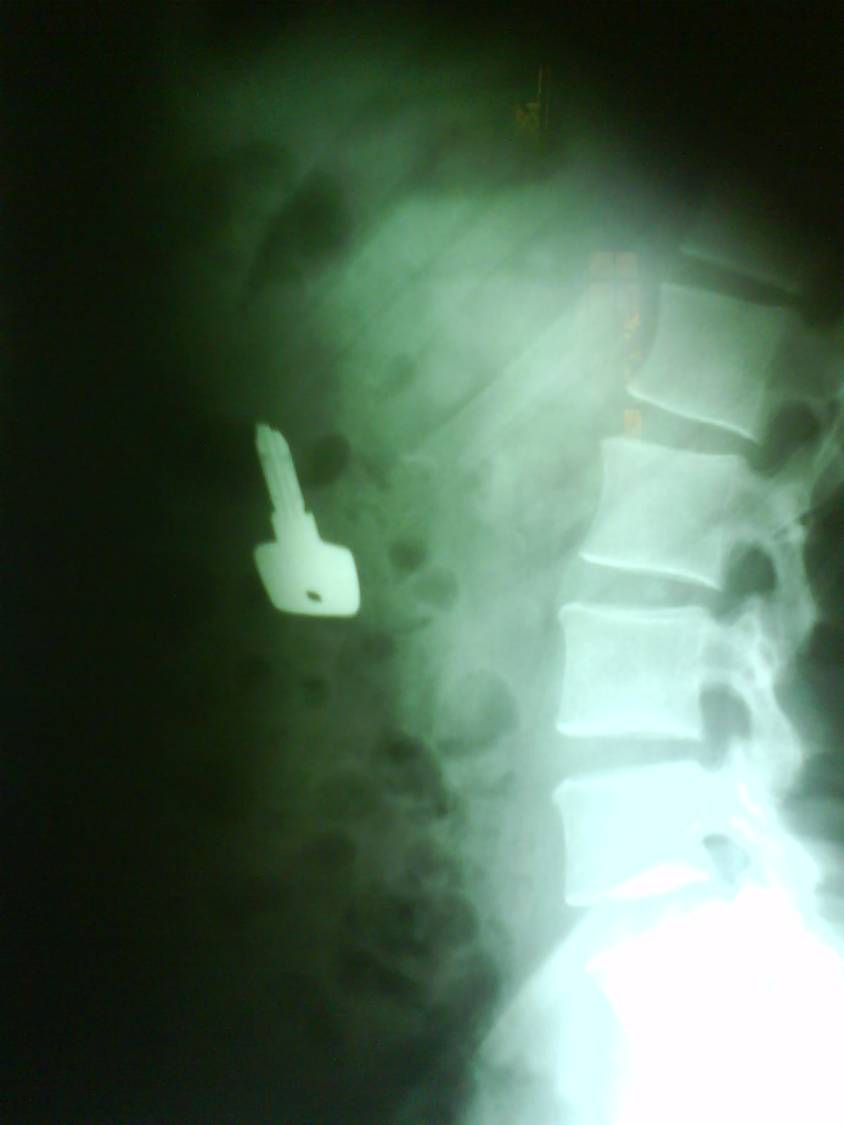

With plain radiography radiopaque foreign objects could be identified. Let’s not forget that images always should be taken at least from two directions. Plain radiographs contain summation images of one projection in order to be able to localize the object orthogonal projections are necessary, fluoroscopy and CT can also be helpful in undetermined cases.

12 A young dancer was partying in the dressing room with his friends. He suddenly swallowed down an object which on the abdominal radiogram proved to be a cupboard key.

Non-radiopaque foreign bodies are more difficult to detect, superficially located objects (e.g. impacted sutures) could be identified by US, deeper located object can be looked up with MRI.